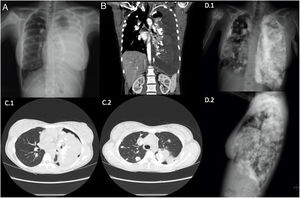

Chest X-ray and computed tomography showed multiple bilateral lung and pleural masses containing calcium, left pleural effusion, and a blastic lesion on the right humeral head (Fig. 1). Pathology study of a lung mass biopsy confirmed the diagnosis of osteosarcoma metastases.

Plain PA chest X-ray (A) and chest-abdominal CT coronal slice (B) at diagnosis, showing massive left pleural effusion, right humeral head blastic lesion, and multiple calcium density images in bilateral pulmonary parenchyma and pleura. Chest CT axial slice (C1 and C2) after drainage of pleural effusion, significant for multiple bilateral metastases in lung parenchyma and pleura, and left pneumothorax. Plain PA and lateral chest X-rays (D.1 and D.2) at 10 months after diagnosis, showing an increase in the number and size of bilateral pulmonary and pleural nodules and masses, left pleural effusion, and an increase in the size of the primary lesion in the right humeral head.